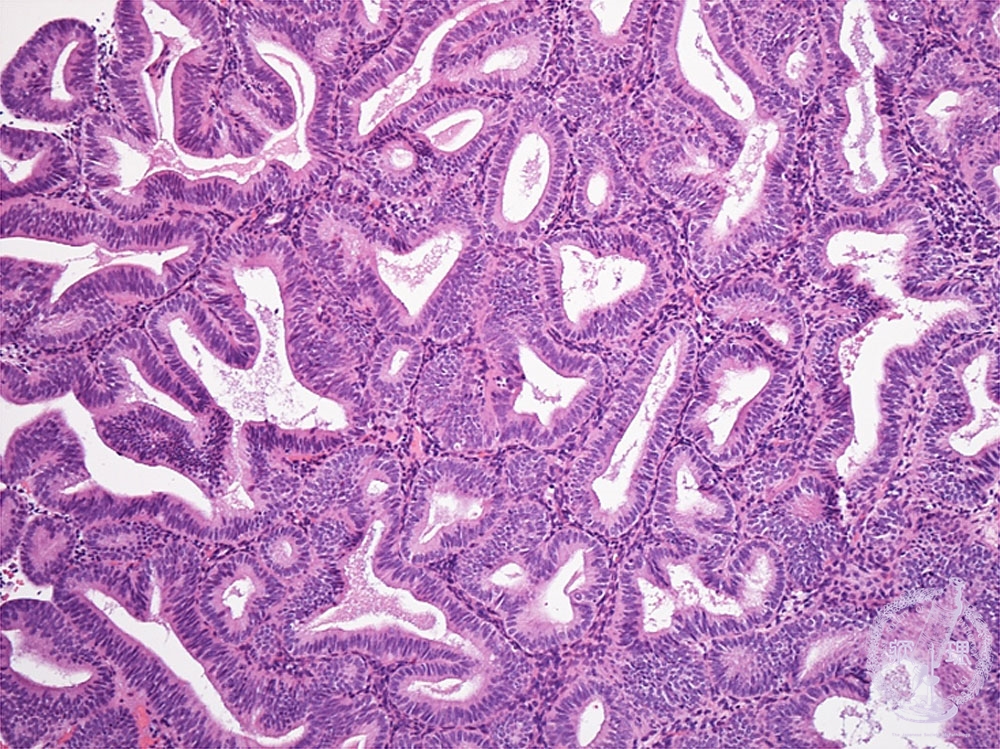

- ★(5)Complex endometrial hyperplasia

Histology (HE stain, intermediate power): Endometrial hyperplasia, complex. Proliferation of endometrial glands without cytologic atypia, forming dense and complicated architecture (yellow dotted line). Stromal proliferation is obscure.